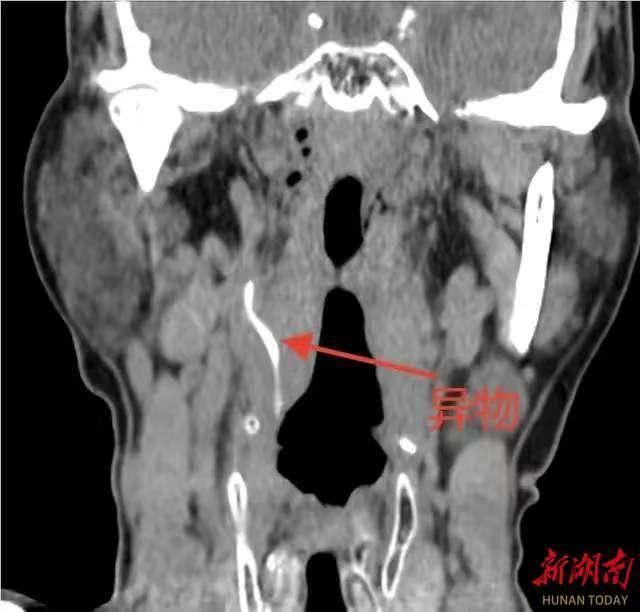

科主任陈志军接诊患者后,结合喉镜情况及详细询问病史,判断该异物可能已深入颈内间隙,经颈部CT三维重建检查,提示咽侧壁异物已穿破黏膜层,深入颈部间隙,且异物尖端距离右侧颈动脉分支仅毫厘之遥。颈动脉是大脑供血的主要通道,一旦被异物刺破或继发感染侵蚀血管,极易引发致命性大出血或脑卒中,手术风险极高。影像警示:异物如同一枚“定时炸弹”,静静地潜伏在颈动脉分支旁,每一次吞咽、颈部活动都可能带来不可预料的危险。面对如此棘手的情况,陈志军科主任迅速启动应急预案,组织血管外科、麻醉科进行多学科会诊。发现风险,经分析,异物位置较深,周围重要血管、神经密布,传统颈外径路手术创伤大、易损伤血管,且可能因术中移位导致二次伤害。

经反复评估,团队最终确定了经口全麻支撑喉镜下异物探查取出术的方案。该微创路径可直达咽部病灶,避免颈部切开,但要求术者具备高超的内镜操作技巧与稳定的心理素质,确保异物取出过程中零移位、零损伤。手术当日,在麻醉团队的保驾护航下,患者进入全身麻醉状态。陈志军科主任借助支撑喉镜充分暴露咽部,于高清内镜视野下,清晰见异物嵌顿处黏膜红肿,周围组织粘连紧密,并小心分离包裹异物的肉芽组织,轻柔松动异物嵌顿方向。

当时,医院利用长柄精细器械,巧妙避开血管搏动区域,以毫米级精度缓缓牵拉,最终将一枚长约4cm的弧形鱼骨完整取出。术中,即刻检查术野无明显活动性出血,颈动脉搏动良好,术后复查CT确认异物无残留,邻近血管毫发无伤。出院当天,受到来自患者及家属的点赞。